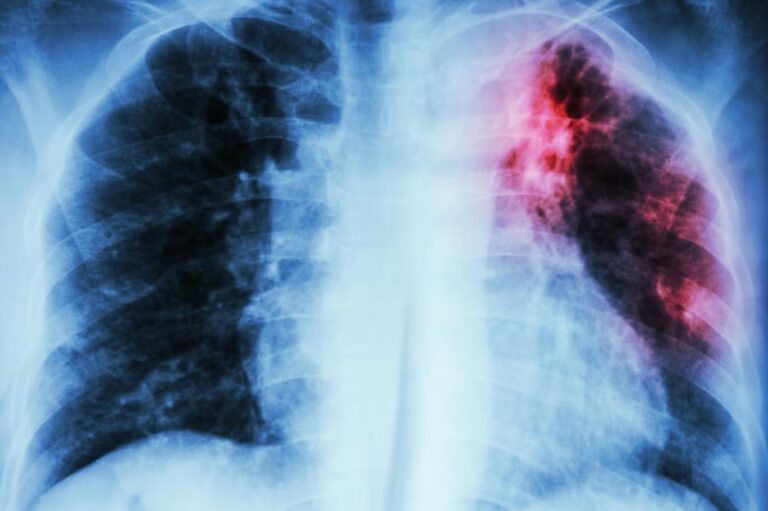

داء السل الفتّاك يشهد تزايدا في الحالات داخل بريطانيا

وبحسب “وكالة الأمن الصحي في المملكة المتحدة” UK Health Security Agency، وعلى رغم تزايد حالات الإصابة بداء السل إلى نحو 5 آلاف حالة في عام 2023 في المملكة المتحدة، إلا أن معدل الإصابات لا يزال منخفضاً، ومن المتوقع استمرار ارتفاع هذه الأرقام خلال العام الحالي.

ما هو داء السل؟

تعرف رئيسة المشورة الصحية في “جمعية الربو والرئة في المملكة المتحدة” Asthma + Lung UK، إيما روباخ مرض السل بأنه “عدوى بكتيرية تصيب عادة الرئتين”، وتقول “يمكن لأي شخص الإصابة بداء السل، ومع ذلك فإن الأشخاص الأكثر عرضة للخطر هم الذين عاشوا خارج المملكة المتحدة حيث تكون معدلات الإصابة بالسل مرتفعة، والدول التي يكون فيها السل أكثر انتشاراً تشمل هي بنغلاديش والصين والهند وباكستان وإندونيسيا”.

وتشير إلى أن “هناك نوعين من مرض السل، “السل الكامن” حيث يكون لديك بكتيريا السل، لكن نظام المناعة في الجسم يسيطر عليها ويمنع نموها، مما يجعلك غير معرض لأي أعراض ولا تشكل خطراً على نقل العدوى للآخرين، وهناك “السل النشط” إذ يفشل نظام المناعة في الجسم في السيطرة على بكتيريا السل، مما يؤدي إلى تطور العدوى وظهور الأعراض”.

وتقول روباش، “قد يكون بعض الأشخاص أكثر عرضة لأعراض خطرة مثل أولئك الذين يعانون ضعف في جهاز المناعة وسوء التغذية ومرض السكري والمدخنين أو مدمني الكحول أو المخدرات، إضافة إلى الأطفال دون سن الخمس سنوات، وعادة ما يصيب مرض السل النشط الرئتين ولكنه قد يؤثر أيضاً في مناطق أخرى من الجسم”.